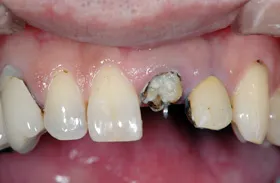

むし歯による前歯欠損の為来院されたケース

■治療前

■歯の根の引き上げ

■治療後

治療のポイント

歯の根の位置を引き上げ、抜歯。その日にインプラント治療へ。

自然の歯と変わらない審美性を取り戻し、非常に満足されています。

| 主訴 | 上顎の真ん中の歯が折れた |

|---|---|

| 治療方法 | 歯の根を引き上げることにより、増骨するので、その後1本のインプラントを埋入し治療した |

| 治療期間 | 約1年 |

| 通院回数等 | 10回 |

| 費用 | 550,000円(税込) |

| リスク・副作用 | 外科治療なしで増骨させた為、治療期間が長くなった |